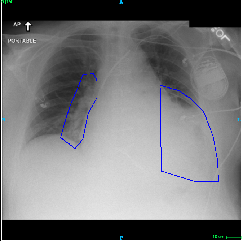

Fig.Β 5: Examples of class activation maps of positive cases. Left to right: image with annotation in blue, no L1 regularization, with L1 regularization, baseline.

Fig. 5 shows examples of class activation maps of positive cases for visual comparisons among the final models. These were produced using the Grad-CAM approach [14]. The images were annotated by an expert for the regions of opacity. Although all models correctly classified the cases as positives, the activation maps of the baseline model were barely correlated with the annotated regions, with more irrelevant hot spots outside the lungs. On the other hand, the activation maps of the models with feature selections were better correlated with the annotation. In other words, these smaller networks seems to be also more focused on the correct regions, which is a step towards explainability. The image in the third row shows that the VGG16 activation map has important components outside the lungs, focusing on English characters on the image. Whereas the reduced networks show more activation in marked areas of the lungs.